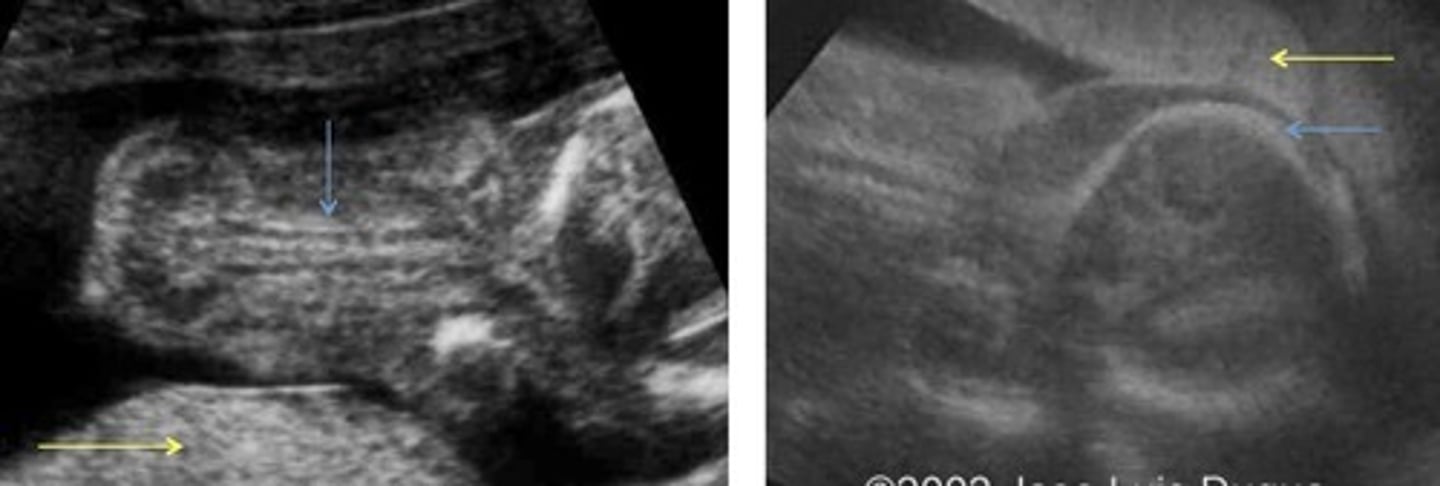

Caudal Regression

Incomplete development of lower half of body

Sacral agenesis

Talipes - cubed feet

Short lower extremities

GU and GI anomalies